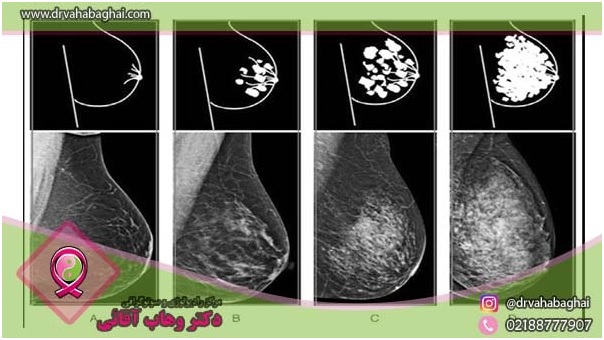

انواع فیبروکیستیک

تشخیص فیبروکیستیک در مرحله اول توسط پزشک و با استفاده از آزمایشات فیزیکی انجام می‌شود. علاوه بر این، انجام ماموگرافی ، تصویر برداری MRIو  یا سونوگرافی می‌تواند به تشخیص دقیق‌تر نوع و ماهیت بافت‌های متراکم پستان کمک کند. کلیه آزمایش‌های مربوط به تشخیص ناهنجاری‌های پستان در کلینیک دکتروهاب آقایی واقع در خیابان ولیعصر با کاردی از رادیولوژیست‌های مجرب انجام می‌شود.

ماموگرافی

اگر پزشک شما متوجه وجود یک توده ضخیم و متراکم در بافت پستان‌ها شود ممکن است انجام آزمایش ماموگرافی دیجیتال تشخیصی را تجویز کند. ماموگرافی با استفاده از پرتوهای ضعیف شده اشعه ایکس انجام می‌شود و به منظور شناسایی دقیق ناهنجاری‌های بافت پستان استفاده می‌شود.